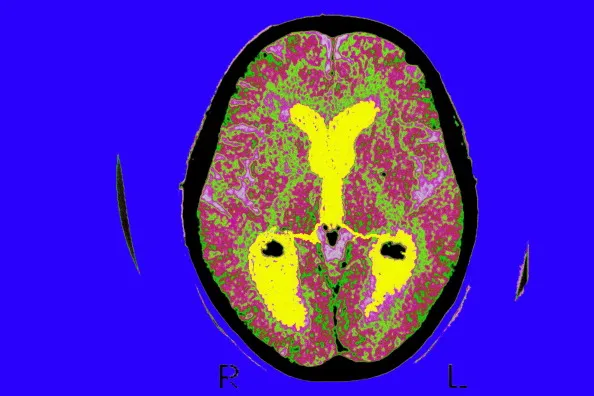

Source: BSIP/UIG via Getty Images